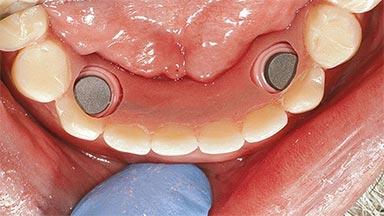

An 83-year-old man presented together with his caregiver at the dental department of the Medical University of Innsbruck, Austria with complaints of swelling in the right maxillary canine area and loss of retention of his 5-years-old mandibular denture. The patient had a significant medical history (20 years) of bipolar affective disorder with moderate depression (F 31.3) and dementia in Alzheimer’s disease (F 00.2). The patient had been in ambulant psychiatric therapy for his depressive illness for the past 20 years. He lived alone and had no children; his sister assisted with daily living. She reported that the patient exhibited compulsive hoarding behavior. In the previous two months, she had noted increasing disorientation and vertigo in the patient. She therefore accompanied him for a medical consultation at the Department of Psychiatry and Psychotherapy of the Medical University of Innsbruck. He was released home after a 6-week inpatient stay.